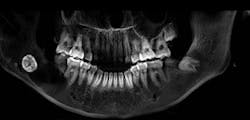

A 13-year-old male was noted by his orthodontist to have an expanding radiolucency encompassing impacted tooth no. 11. The patient was without complaint, and his medical history was otherwise unremarkable. A CT scan revealed a multilocular radiolucency extending from the maxillary midline to the area of the left permanent second molar and expanding into the left maxillary sinus. Cortical expansion in the area of the lesion was notable and all adjacent teeth were vital.